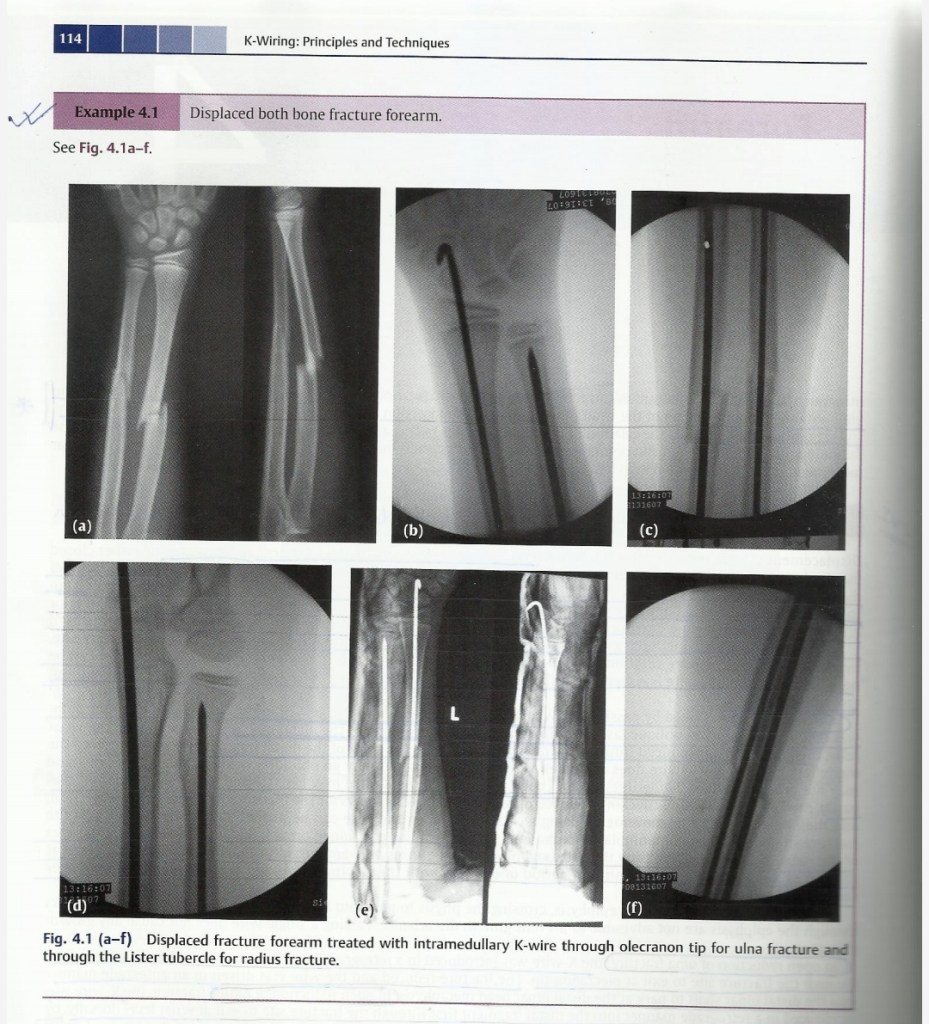

Lecture Pediatric Orthopedic injuries